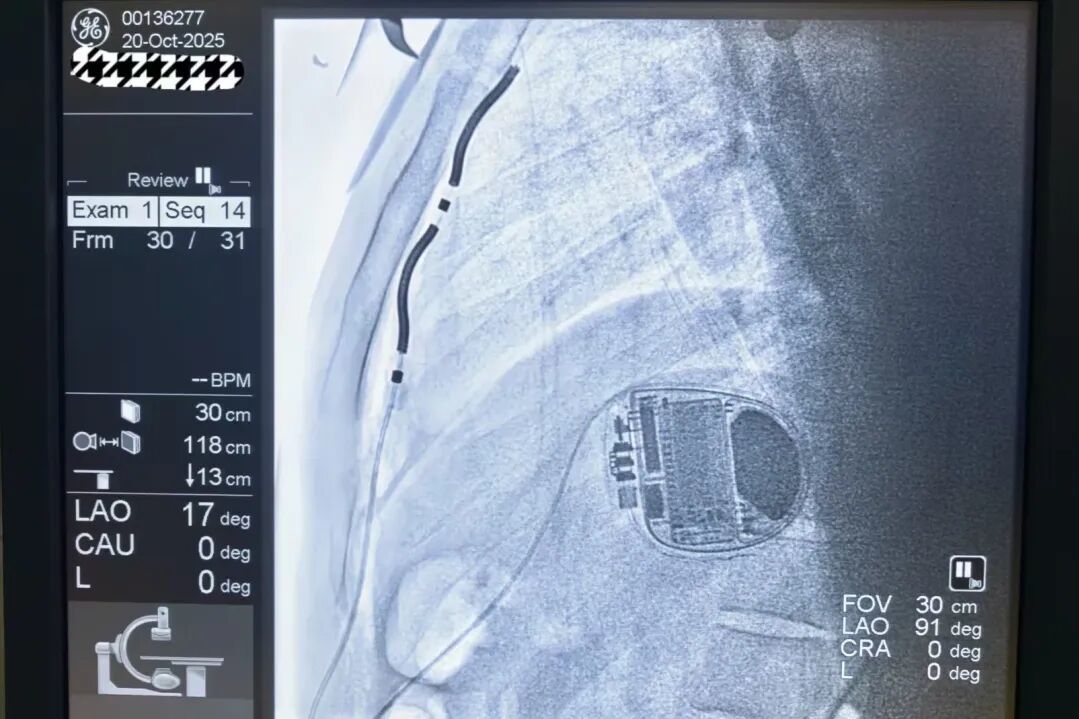

装置植入完成

经过充分的术前评估和准备,科室团队凭借精湛的技术,于10月20日成功为张某实施了EV-ICD植入手术。手术过程顺利,患者目前恢复状况良好。